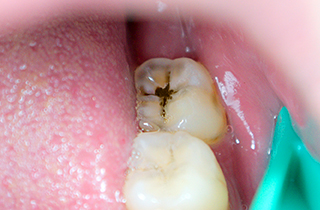

Caries treatment for decay visible during clinical examination

Decay limited to the enamel, the outer layer of the tooth, with little or no pain.

Resin Restoration